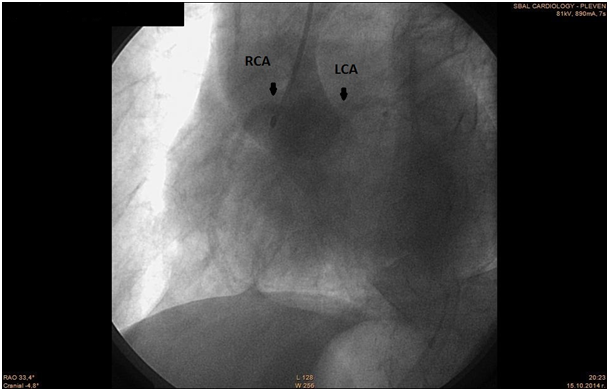

The patient was transferred to the Catheterization Laboratory in order to undergo coronary angiography. The coronary angiography revealed normal anatomy of Left Main Coronary Artery, LAD- 80% mid segment stenosis. LCx - irregularities. RCA - anomalous origin from the left Valsalva sinus. 50% mid segment stenosis, distal occlusion with thrombus. PCI was performed with guiding catheter XB 3.5 6F, coronary guide wire Terumo Runthrough 0.014". Predilation with balloon 2, 75/20 mm and implantation of two drug eluting stents 2, 75/28 mm with overlapping. Post-dilation at the site of overlapping with the balloon of the second stent.

The patient was previously hospitalized for chronic heart failure NYHA class III and ventricular fibrillation, which was treated with a synchronized shock. She also has arterial hypertension present for the past 20 years, permanent atrial fibrillation and type 2 diabetes. For these conditions she was on the following medication therapy: Bisoprolol Fumarate, Telmisartan, Amiodarone, Gliclazide, Metformin, Acenocoumarol, Tavipec and Azithromycin (Figure 46). The cause of the present ischemia is not a result of a mechanical compression of the artery, but is a result of atherosclerosis and plaque rupture with subsequent development of myocardial infarction (Figure 7 & 8).

Figure 5 LCA & RCA.